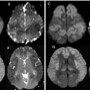

Figures A B, C & D: Axial section diffusion weighted and corresponding apparent diffusion co-efficient images showing symmetrical diffusion restriction in bilateral cerebral cortices with sparing of perirolandic regions (arrows).

Figures E, F, G & H: Axial section diffusion weighted and corresponding apparent diffusion co-efficient images showing symmetrical diffusion restriction in bilateral cerebral cortices predominantly in the insular cortices (curved arrows) and thalami (arrow heads) with sparing of occipital cortices (asterisks).

- Typical MRI findings – Bilateral symmetrical cortical signal abnormalities on FLAIR and DWI/ADC, predominantly in insula and cingulate gyrus with sparing of occipital and perirolandic cortices. Basal ganglia, thalami and brain stem are additional sites of involvement. It is also emphasized that signal changes distribution is independent of origin of hyperammonemia.